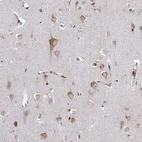

Immunohistochemical staining of human kidney shows strong cytoplasmic granular positivity in cells in tubules.